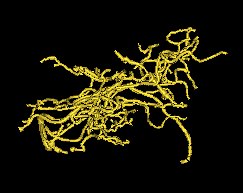

The data are from a Magnetic Resonance Angiography (MRA) study of brain images of a set of human subjects of both sexes, ranging in age from to , which can be found at Handle (2008). A tube tracking algorithm was applied to the MRA images resulting in a segmentation of arteries as shown in the images in Figure 1. See Aylward and Bullitt (2002) and Bullitt et al. (2010) for details of this study.

The artery system feeding the brain can be divided into component systems according to the areas they feed in the brain. In the figure, these systems are colored in gold for the back, cyan for the left, blue for the right and red for the front regions. Each of these regions are studied separately, giving rise to data sets. For each of these regions, the vessel structure is reduced to only its topological (connectivity) aspects by representing it as a simple binary tree. Each vessel tube between two split points is converted into a node in the binary tree, and the two tubes after the split are the children nodes of the first node. Figure 1 gives an example of this conversion. The root node at the top represents the initial fat gold tree trunk shown near the bottom of the figure.